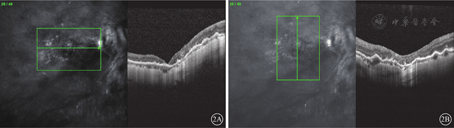

患者女,51岁。因右眼被木棍击伤后视力下降1个月余来我院眼科就诊。既往有高血压病史10年。眼部检查:右眼视力手动/眼前,左眼视力1.0。角膜透明,前房Tyn(++),晶状体密度高;玻璃体腔少量积血;全视网膜脱离,较僵硬,赤道部10点时钟位可见2 DD大小马蹄孔。左眼眼前节及眼底检查未见明显异常。诊断:右眼视网膜脱离、钝挫伤。行右眼玻璃体切割手术(PPV),手术中剥除黄斑区内界膜(ILM),周边张力较大视网膜予以松弛性切开。手术后3个月复查发现黄斑巨大裂孔伴视网膜脱离;因黄斑区视网膜脱离较高,未行黄斑OCT检查。再次行PPV联合自体视网膜神经上皮层移植手术。手术方法:曲安奈德染色剥除玻璃体后皮质,吲哚青绿(ICG)染色撕除残余增生膜及ILM,剥离周边可见的视网膜表面及下方增生条索,张力较大处视网膜予以切开。平镜下对比裂孔大小及形状(图1A);于颞下方8点时钟位周边部视网膜,避开视网膜血管区域,ICG染色,勾勒出与黄斑裂孔大小接近的视网膜神经上皮层组织,垂直剪取该视网膜组织(图1B)并移植到黄斑裂孔处,填充硅油;取出视网膜神经上皮层处予以激光光凝,植入视网膜神经上皮层裂孔处不予激光光凝封闭。手术后保持俯卧位1个月。手术后3个月行硅油取出手术。手术前黄斑OCT检查,视网膜复位良好,黄斑裂孔最窄处直径1213 μm,最宽处直径1519 μm;手术中见视网膜在位。硅油取出手术后1周复查,右眼视力数指/眼前;眼压15 mmHg(1 mmHg=0.133 kPa);晶状体轻度混浊。眼底彩色照相,视网膜复位良好,隐约可见移植视网膜形态与原裂孔基本吻合,可见椭圆形裂孔轮廓(图1C)。黄斑OCT检查,颞侧移植视网膜神经上皮层与原视网膜连接处菲薄,其他方位各层吻合良好,但未见椭圆体及嵌合体带(图2)。因患者自身原因未行眼电生理检查。

Duker等[1]根据OCT测量的裂孔最窄处直径将黄斑全层裂孔分为小、中、大。裂孔直径<250 μm为小裂孔,250 μm<裂孔直径≤400 μm为中裂孔,>400 μm为大裂孔。本例患者裂孔最窄处直径已超过1000 μm。对于裂孔直径>1000 μm的巨大黄斑裂孔仅行PPV和ILM剥除黄斑裂孔难以闭合[2,3]。ILM翻转以及游离ILM填充或晶状体囊膜填充虽然可有效治疗黄斑裂孔并降低发生视网膜脱离的风险[4,5,6,7],但本例患者黄斑裂孔最窄处已超过1000 μm,ILM难以做到有效填充,并且患者既往已行ILM剥除且晶状体较透明。因此,我们采用自体视网膜神经上皮层移植进行治疗,截取面积与黄斑裂孔大小基本吻合的视网膜神经上皮层组织填塞到黄斑裂孔中,在裂孔中形成相对封闭环境,通过RPE主动转运功能,将视网膜下液体转运至裂孔外,视网膜恢复贴复,促进裂孔闭合。所截取的视网膜神经上皮层,其内含有丰富的毛细血管网,相对于ILM和晶状体囊膜,可以更好地与周围视网膜组织愈合。从厚度上,所填充的视网膜神经上皮层与周围视网膜厚度接近,更有利于解剖结构的恢复。而ILM及晶状体囊膜在填充过程中,如果填塞过少,可能从裂孔中脱离;填塞过多,则会形成"山峦"样拱形结构,对手术后裂孔的愈合不如视网膜神经上皮层。患者手术后黄斑OCT检查提示,除颞侧有缝隙状视网膜菲薄区域外,其余各方位完美愈合,所移植的视网膜神经上皮层与原视网膜组织从神经纤维层到外核状层均吻合良好;但未发现正常椭圆体带组织层。因此,对于移植的视网膜神经上皮层是否具有一定的视功能尚需大样本研究和长期随访。